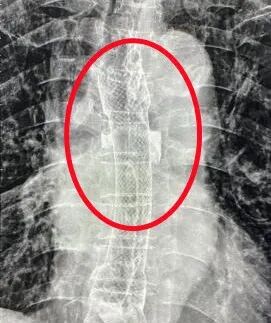

普外科主任周志伟通过详细询问患者病史、全面体格检查、查阅相关CT及胃镜检查报告,鉴于患者年龄大、体质弱、营养状况差等因素,开启绿色通道将患者收住院。经过医院多学科专家联合会诊,确定了为患者施行“食道支架植入术的微创治疗”方案。此次手术在DSA引导下进行,普外科专家团队用精湛娴熟的操作技术,经口把食道支架成功放置到病灶部位,整个手术历时30分钟,期间患者无明显不适。

普外科主任周志伟介绍,我国是消化道肿瘤高发国家,每年食道癌、胃癌、结肠癌、直肠癌都会造成较高的死亡率。消化道肿瘤往往会造成消化道阻塞,影响进食或排便,而食道癌最大的问题是患者进食困难。此次市五院开展的食道支架植入术是针对各种原因引起的食道狭窄进行扩张后放置内支架的技术。手术选用的支架具有良好的生物相容性和耐腐蚀性,同时具有记忆特性和超弹性,可使梗阻部位恢复通畅。另外,支架表面覆有医用硅橡胶膜,可有效防止食管壁肿瘤进入支架内。通过开展此项新技术,帮助肿瘤患者陈伯减轻了痛苦,提高了生活质量,延长了生命周期。今后,可让周边此类患者就近得到标准化、高质量的医疗服务。